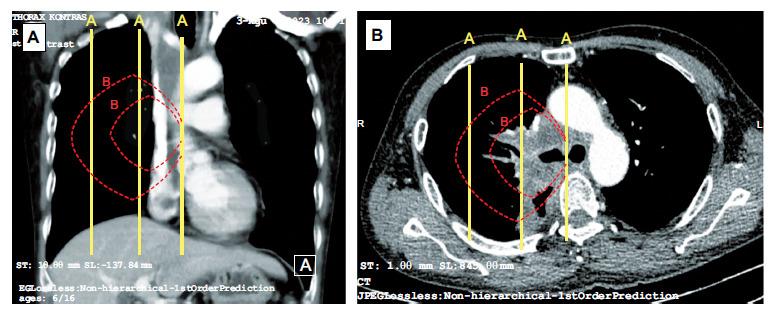

This was an observational cross-sectional study of PCLTs, defined as tumors in direct contact with hilar structures or located within the inner two-thirds of the hemithorax. We gathered demographic and clinical data, as well as data on bronchoscopy assessment and histopathology type. Tumor stage, symptoms of superior vena cava syndrome, and enlargement of lymph nodes in the paratracheal and subcarinal regions were also documented.

方法

这是一项对PCLTs的观察性横断面研究,PCLTs定义为与肺门结构直接接触或位于半侧胸腔内三分之二区域的肿瘤。我们收集了人口统计学和临床数据,以及支气管镜评估和组织病理学类型的数据。还记录了肿瘤分期、上腔静脉综合征症状以及气管旁和隆突下区域淋巴结肿大情况。